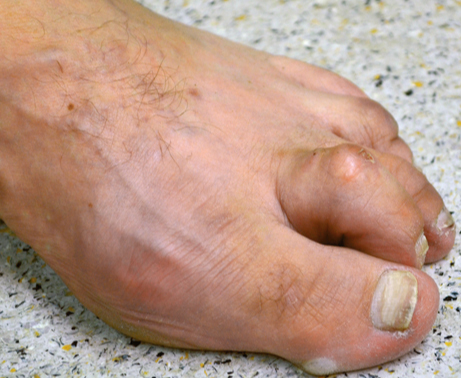

Der Hallux valgus (Ballenzehe)

Beim Hallux valgus - im Sprachgebrauch häufig Ballenzehe genannt - handelt es sich um eine Abweichung der Großzehe nach außen, kleinzehenwärts. Diese Fehlstellung tritt häufiger bei Frauen auf. Die genaue Ursache ist nicht geklärt, sicherlich spielen falsches Schuhwerk und Erbanlagen eine große Rolle. Die unterschiedlichen Ausprägungen sind durch eine zunehmende Fehlstellung, verbunden mit Schmerzen, gekennzeichnet.

Von einer operativen Korrektur ohne Vorhandensein von Schmerzen, d. h. aus rein kosmetischer Sicht, ist abzuraten. Bei Auftreten von Schmerzen im Bereich der Großzehe ist die operative Vorgehensweise jedoch die einzig dauerhafte therapeutische Möglichkeit.

Krallenzehe

Die Krallenzehe oder Hammerzehe beschreibt eine Fehlstellung bzw. Verkrümmung der Kleinzehen. Durch zunehmende Verkürzung zunächst der Beugesehne im Mittelgelenk, dann der Strecksehne im Grundgelenk, kommt es zu einer Verkrümmung der Zehe. Hierdurch entstehen Schmerzen und Verhornungen unter dem Vorfußballen, sowie schmerzhafte Druckstellen über den Mittelgelenken (Hühneraugen). Diese Fehlstellung lässt sich meistens nur operativ korrigieren. Durch eine Verlängerung der Strecksehne und Lösung der Gelenkkapsel, verbunden mit einer Versteifung im Zehenmittelgelenk, wird die Zehe dauerhaft begradigt. Die Druckstellen und Schmerzen gehen zurück.